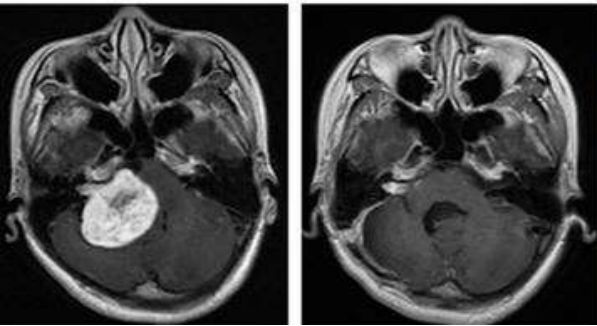

而质子是相对较重的带正电的粒子,它们在击中目标时停止。而X射线束由光子组成,光子是几乎没有质量的粒子,因此它们会一直穿过身体,包括健康的组织。质子释放的能量是远远大于普通放疗中所使用的X射线的,X射线的能量为4~18MeV,而质子的能量为70~230MeV,如果将X线比作篮球,那么质子线就是铅球,下面这张图形象的说明的质子的物理学特性,我们可以清除的看到,质子线在红色肿瘤的位置释放最大的能量之后迅速将剂量降为零,几乎不会损伤到后面的正常心脏组织,而X线照射的特点却是初进人体时剂量最大,逐步衰减,如果肿瘤部位较深,可能X线在肿瘤部位的照射剂量仅剩50%左右,更为严重的是,X射线还会对肿瘤后面的正常心脏组织造成辐射伤害。因此,只要允许放射治疗的肿瘤都可以考虑质子治疗来将正常组织的伤害降到最低。